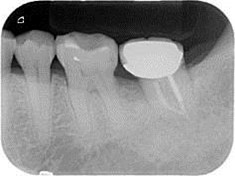

術後一年之全口X光片, #37近心側可見明顯骨充填與放射線密度增加。 牙周再生手術完成一年後追蹤,全口牙齦發炎狀況改善,牙周組織呈現健康狀況。#37金屬燒附陶瓷牙冠製作完成。